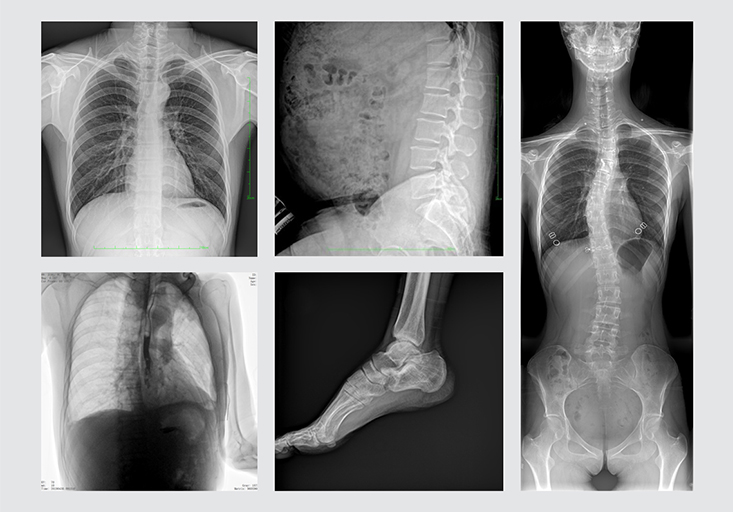

清晰的臨床圖像

多功能動態DR展示視頻